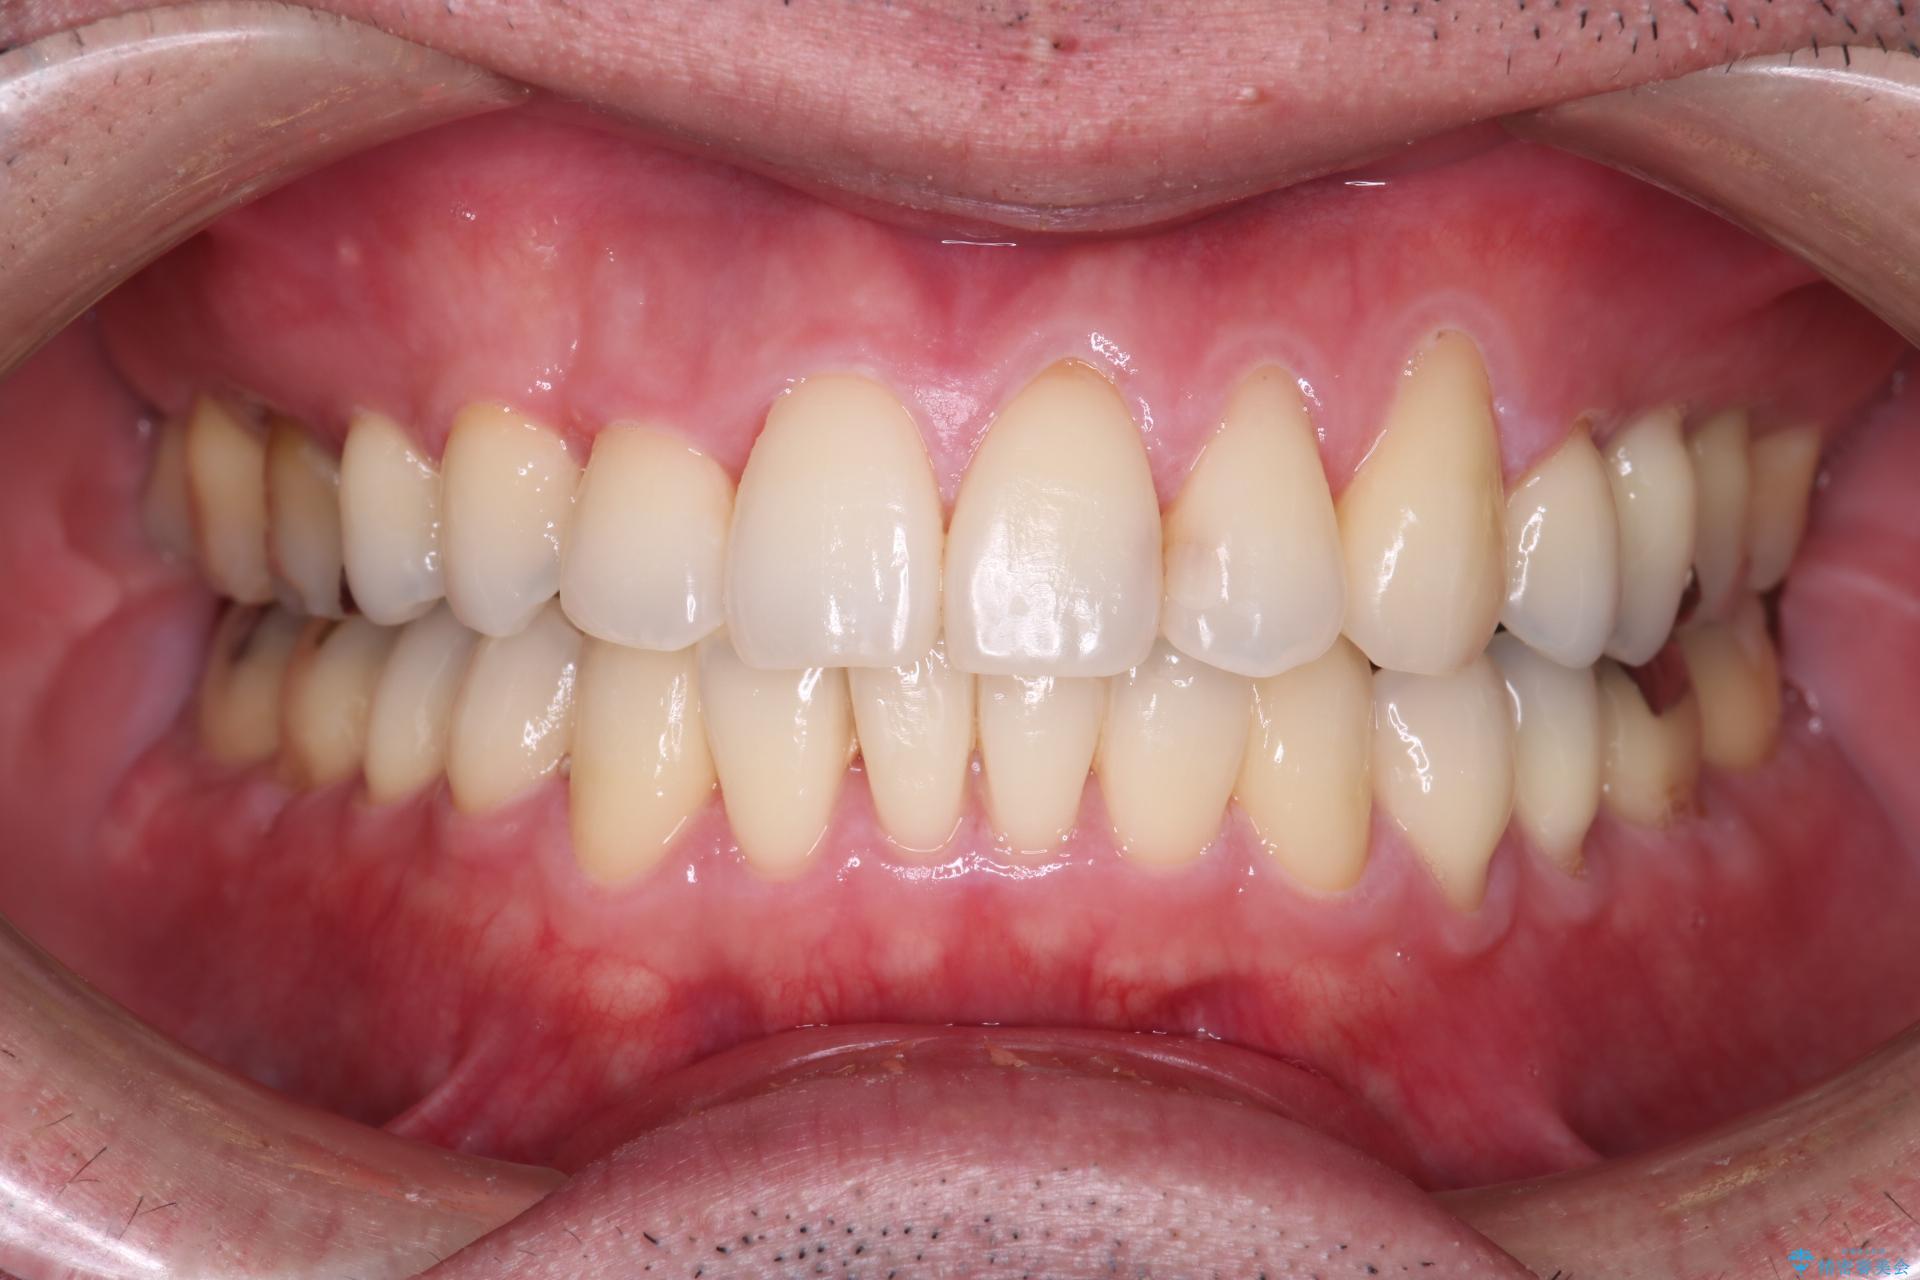

抜歯の本数を最小限に抑えたことで、治療計画も1年5ヶ月と短期間で終了することができ

主訴である前歯のがたつきも改善され綺麗な歯並びになりました。

矯正の装置を除去したタイミングで、ホワイトニングも行うことで歯の色味も白くなりました。